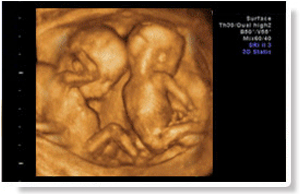

此期间胎儿肢体及各主要脏器已全部发育,且羊水较多、胎儿活动度较大,能全面检测宝宝发育情况,适合做四维彩超全面筛查胎儿畸形

血细胞放大1000倍,4D清晰成像,辐射仅为手机辐射的万分之一